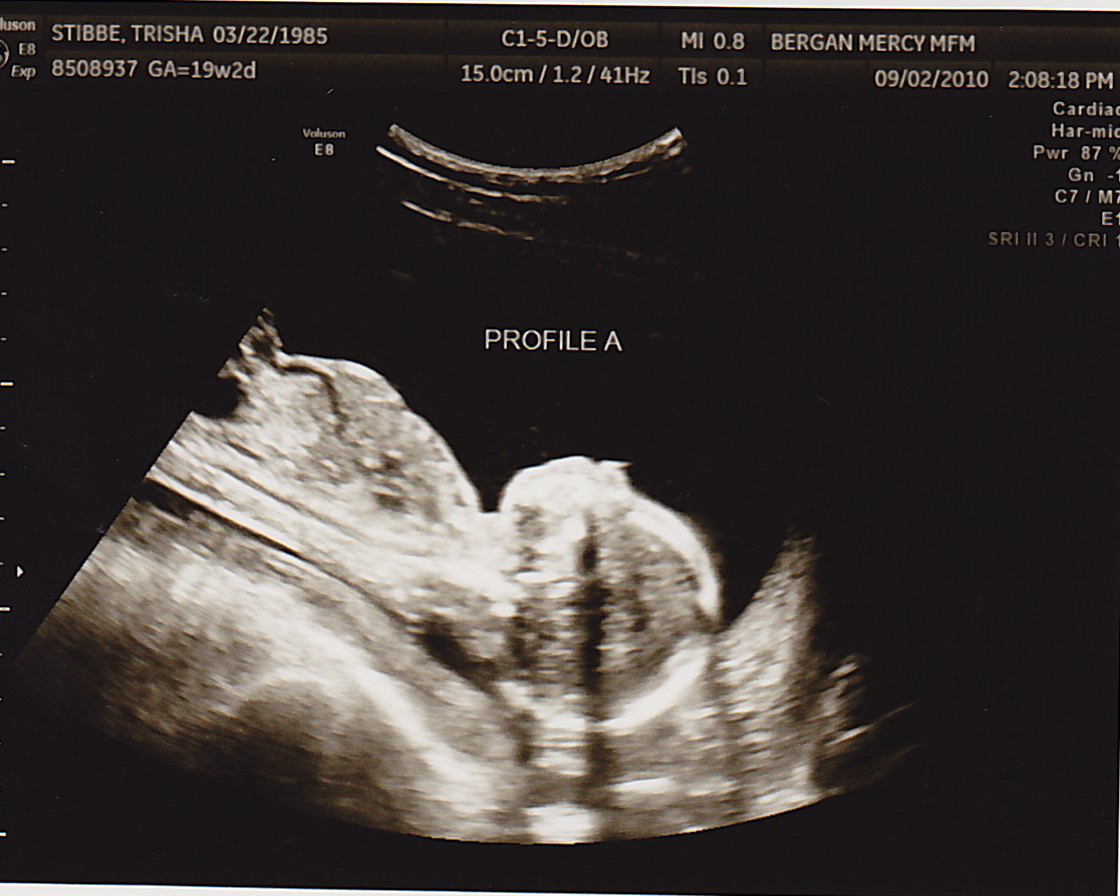

TODAY was a great appointment- we found out Baby B had a lot more fluid around himself!!! That means I didn’t have to have more fluid drained (at least for today). Baby A was 8oz and Baby B was 6oz. This is still good news, because two weeks ago Baby A was 6oz and Baby B was 4oz. As long as they’re both gaining the same amount of weight from here on out, we’re very positive everything will be okay. The difference between them just needs to continue to lessen.